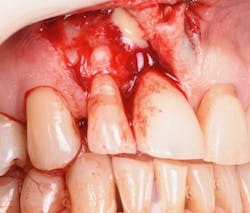

Figure 9: Initial presentation prior to crown lengthening

Figure 10: Immediate post-op hard- and soft-tissue crown lengthening with laser